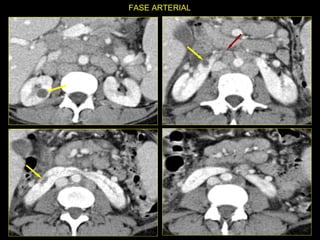

Caso # 4 ♀ , 5ta década de la vida  Presenta dolor abdominal difuso sin poder determinarse la causa clínicamente por lo que se solicita la TC Estudio con cortes axiales y coronales demostrándose  fases arterial y venosa.

FASE ARTERIAL FASE VENOSA

Hallazgos Caso #4: Riñón en herradura. Área cuneiforme de disminución de la atenuación en el istmo del riñón en herradura en relación con proceso inflamatorio focal que es exquisitamente demostrada en las RMP coronales.  Lesiones hipodensas, redondeadas en riñón derecho, las cuales no muestran aumento en el valor de atenuación con la ministración del medio de contraste en relación con quistes Bosniak I.